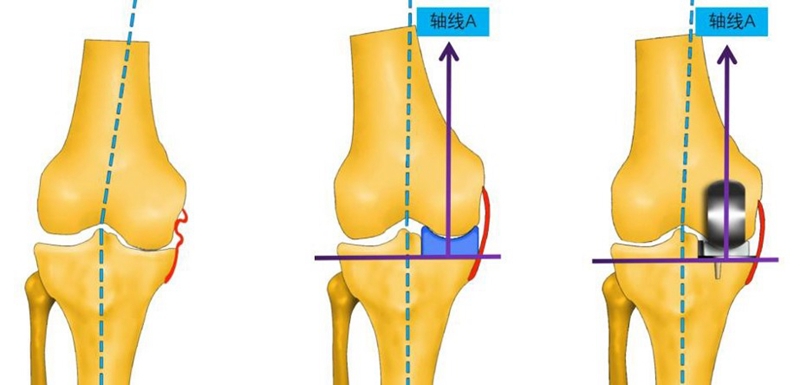

运动学对位对线定位技术的原理核心为:①胫骨精确截骨,保证力学;②spacer充分填充,恢复到自然状态。

操作要点(画好线,钻好孔)

①屈曲位,钻孔导向器底面紧坐在胫骨截骨面,贴住股骨远端;

②钻孔方向指向与轴线A平行;

③通过视窗核实钻孔贴于假体中心线上;

④钻孔位于股骨内髁远端关节面中心线。